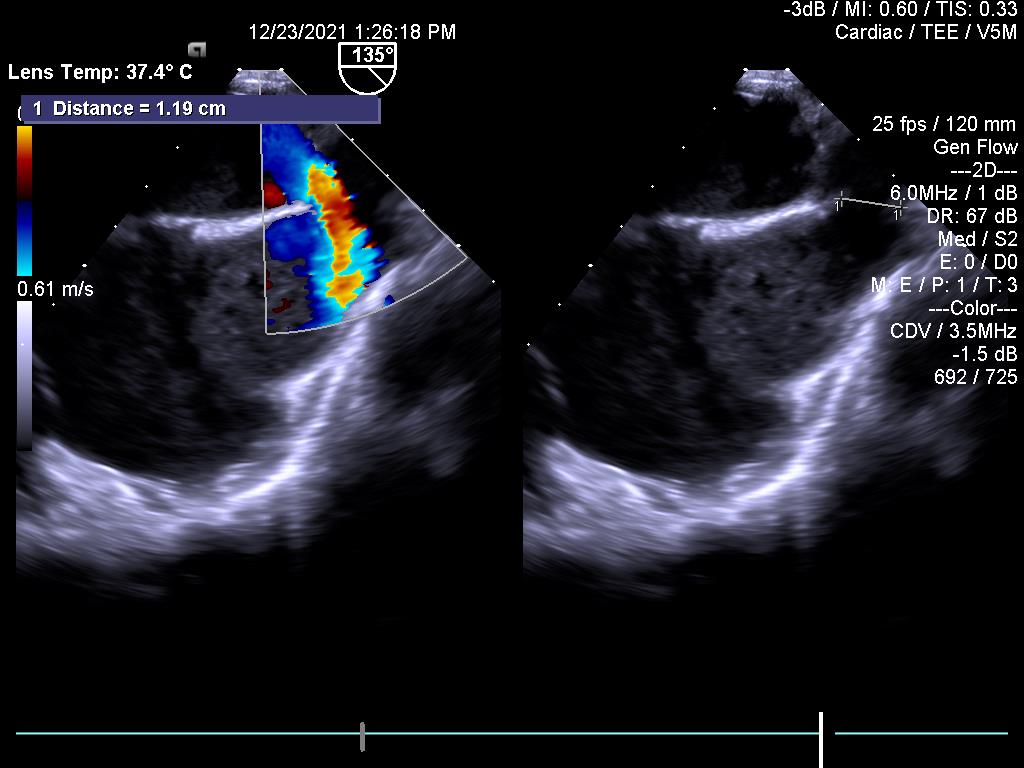

3.Huyết khối tiểu nhĩ trái trên bệnh nhân hẹp van 2 lá (không thấy được trên siêu âm tim qua thành ngực)